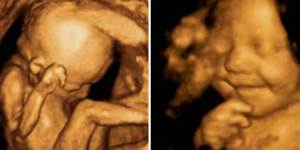

- Ciencia: Debatir el concepto «persona» es un argumento abstracto, el concepto «vida» no lo es. La ciencia lo afirma indiscutiblemente, en multitud de fuentes, que la vida comienza en la concepción. También es importante tener en cuenta la rapidez con que se desarrolla un niño dentro de la madre. Los hitos del desarrollo fetal del primer trimestre extraídos de la clínica Mayo incluyen:

Fertilización e implantación (el proceso comienza aproximadamente 2 semanas desde el último período menstrual). Semana 3 (5 semanas desde LMP): el cerebro, la médula espinal y otros órganos comienzan a formarse. Semana 4: (6 semanas desde LMP): las características faciales comienzan a aparecer, el corazón del bebé bombea sangre. Semana 9 (11 semanas a partir de la LMP): los genitales se desarrollan. El comienzo de la vida es un hecho indiscutible y es una medida efectiva y justa a partir de la cual se puede configurar la política.